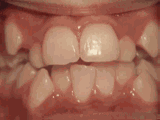

开颌通俗来讲就是咬牙时无法紧闭,所以门牙功能基本作废,无法切割食物。

深覆合指的是上牙边沿覆盖下牙超过1/3,俗话说的天包地。

前牙反合通俗来讲就是下牙边沿覆盖上牙超过1/3,俗话说的地包天,一般会引起脸型的变化,出现弯月脸。